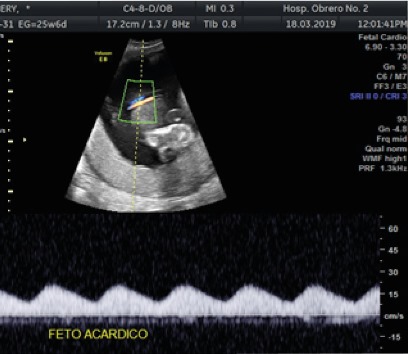

<body><![CDATA[<p align="justify"><font size="2" face="Verdana, Arial, Helvetica, sans-serif">La etiolog&iacute;a de la secuencia TRAP no se conoce con exactitud. Se ha propuesto la alteraci&oacute;n de la organog&eacute;nesis en respuesta al flujo reverso a trav&eacute;s de las anastomosis arterio-arterial o veno-venosas anormales, que lleva a hipoxia prematura y alteraci&oacute;n del desarrollo cardiaco<sup>2,10</sup>, &nbsp;resultando que sangre desoxigenada de la arteria umbilical del &rsquo;&rsquo;gemelo bomba&rsquo;&rsquo; fluya retr&oacute;gradamente hacia las arterias umbilicales (o arteria porque a menudo solo hay una) y vasos il&iacute;acos del gemelo acardio, perfundiendo as&iacute; con sangre desoxigenada la parte inferior del cuerpo en una extensi&oacute;n mucho mayor que la parte superior, lo que da lugar a una masa gemelar muy an&oacute;mala<sup>2,3</sup>. El resultado es un espectro de malformaciones, anomal&iacute;as de reducci&oacute;n de tejidos previamente existentes y morfog&eacute;nesis incompleta de tejidos principalmente en la parte superior del cuerpo<sup>3,6</sup>. Los gemelos acardios son verdaderos par&aacute;sitos que dependen totalmente del gemelo bomba para su irrigaci&oacute;n sangu&iacute;nea y no tienen tejido placentario funcional propio<sup>5</sup>. El gemelo bomba que se perfunde a s&iacute; mismo y adem&aacute;s al ac&aacute;rdico desarrolla una insuficiencia card&iacute;aca congestiva con hidrops fetal y polihidroamnios, lo que suele finalizar en parto prematuro u &oacute;bito<sup>4</sup>. <o:p></o:p> </font></p>      <p align="justify"><font size="2" face="Verdana, Arial, Helvetica, sans-serif">El gemelo acardio puede poner en peligro el bienestar del gemelo bomba en funci&oacute;n de tres mecanismos distintos: Primero, la masa gemelar ac&aacute;rdico al crecer aumenta el volumen intrauterino y, por consiguiente, el riesgo de parto pretermino; la edad gestacional media en el momento del parto es de 31 semanas. Segundo, el fen&oacute;meno del robo vascular puede conducir a una insuficiencia cardiaca de gasto elevado e hidrops con polihidramnios, e incluso muerte intrauterina. Por &uacute;ltimo, el gemelo acardio desoxigena a&uacute;n m&aacute;s la sangre ya de por si desoxigenada del gemelo bomba, esta sangre desoxigenada regresa a trav&eacute;s de una anastomosis veno-venosa hacia el gemelo bomba y reduce m&aacute;s su nivel de ox&iacute;geno, causando hipoxia cr&oacute;nica y restricci&oacute;n del crecimiento<sup>5,10</sup>. <o:p></o:p> </font></p>      <p align="justify"><font size="2" face="Verdana, Arial, Helvetica, sans-serif">El diagn&oacute;stico prenatal se basa en el reconocimiento de un feto de aspecto normal y otro feto con aspecto muy an&oacute;malo o una masa amorfa de tejido en un embarazo monocori&oacute;nico<sup>2</sup>. El Doppler en color muestra flujo sangu&iacute;neo en la masa acardia y en su cord&oacute;n umbilical con <i>direcci&oacute;n de este flujo sangu&iacute;neo invertida, que se dirige hacia el gemelo acardio</i><sup>2,610</sup>. El gemelo ac&aacute;rdico es incompatible con la vida sin importar su extensi&oacute;n, mientras que el pron&oacute;stico en el gemelo bomba, anat&oacute;micamente sano, var&iacute;a considerablemente<sup>10</sup>. <o:p></o:p> </font></p>      <p align="justify"><font size="2" face="Verdana, Arial, Helvetica, sans-serif">El objetivo de este art&iacute;culo es revisar los aspectos b&aacute;sicos y el estado actual de esta condici&oacute;n, incidiendo principalmente en el diagn&oacute;stico y el manejo expectante. <o:p></o:p> </font></p>         <p align="justify"><font size="3" face="Verdana, Arial, Helvetica, sans-serif"><b>Reporte de caso        <o:p></o:p> </b></font></p>        <p align="justify"><font size="2" face="Verdana, Arial, Helvetica, sans-serif">El siguiente caso presentado es de una paciente de 35 a&ntilde;os de edad, natural de Cochabamba, ocupaci&oacute;n maestra de escuela, con antecedente de una ces&aacute;rea anterior seis a&ntilde;os antes, sin otros antecedentes personales de importancia m&eacute;dica, cuyo cuadro inicia cuando cursaba su segundo embarazo, por un control ecogr&aacute;fico de la semana 13 que informaba: <i>aparente embarazo gemelar monocorial biamni&oacute;tico con un feto normal y el otro posible ac&aacute;rdico</i>. Ante tal hallazgo realiz&oacute; otros dos estudios por otros dos m&eacute;dicos que informaron como embarazo gemelar con un feto vivo y el otro obitado. <o:p></o:p> </font></p>      <p align="justify"><font size="2" face="Verdana, Arial, Helvetica, sans-serif">El estudio morfol&oacute;gico realizado a las 19 semanas, en servicio particular, ya conclu&iacute;a como: <i>embarazo gemelar monocorial biamni&oacute;tico con un feto normal y el otro ac&aacute;rdico</i>. Con este resultado acudi&oacute; al servicio de Ginecolog&iacute;a y obstetricia del Hospital Obrero No 2 de donde fue referido a la Unidad de Medicina fetal al que acudi&oacute; reci&eacute;n en la semana 21. En esta unidad, se practic&oacute; un nuevo estudio ecogr&aacute;fico encontr&aacute;ndose los siguientes hallazgos: <i>secuencia TRAP en gestaci&oacute;n gemelar monocorial biamni&oacute;tico con un feto vivo normal (feto bomba) sin afectaci&oacute;n hemodin&aacute;mica y el otro feto ac&aacute;rdico </i>(figura 1).</font></p>     <p align="center"><img src="/img/revistas/gmb/v43n2/a18_grafico_1.jpg" width="408" height="354"></p>     <p align="center"><font size="2" face="Verdana, Arial, Helvetica, sans-serif"><b>Figura 1.</b> Demostraci&oacute;n por Doppler de flujo en la arteria umbilical    <br> &uacute;nica hacia el feto acardio.</font></p>     ]]></body>